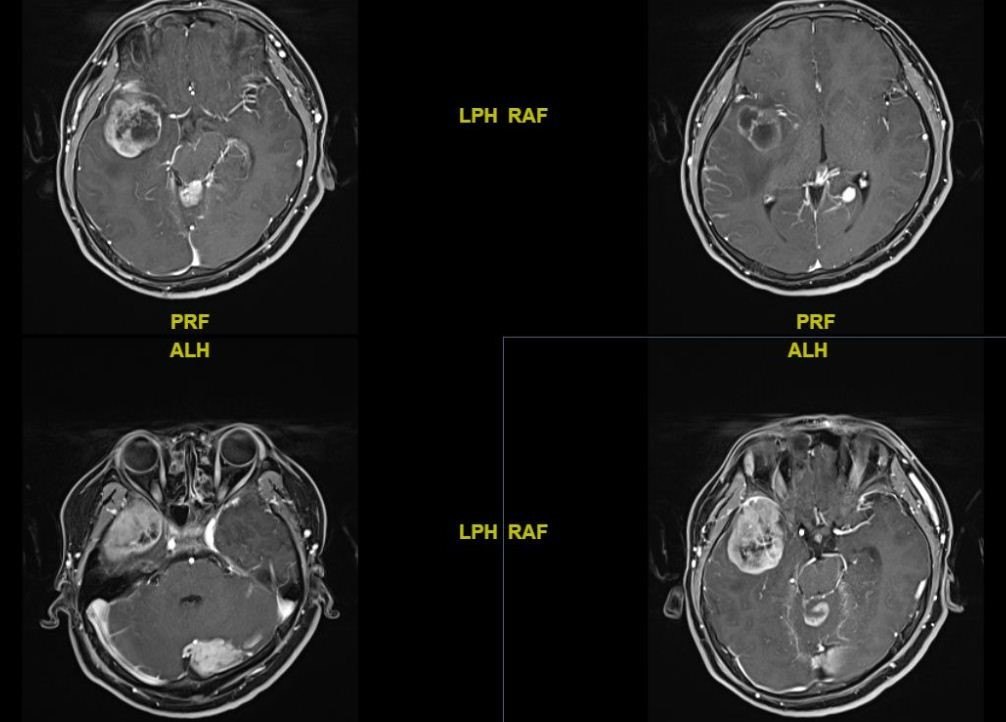

该患者男,19岁,因头痛头晕1个月前来就诊。头颅MRI示:幕上、幕下多发病变。术前诊断:转移瘤?淋巴瘤?行右侧颞叶脑立体定向活检术,病理提示:中枢胚胎性肿瘤。

中枢神经系统胚胎性肿瘤指有未分化或低分化的神经外胚层细胞形成的高度恶性的肿瘤,具有多向分化的潜能。该病比较少见,占中枢神经系统肿瘤的0.1%,好发于儿童和青少年。该病预后不良,明确诊断仍然依靠手术或活检。